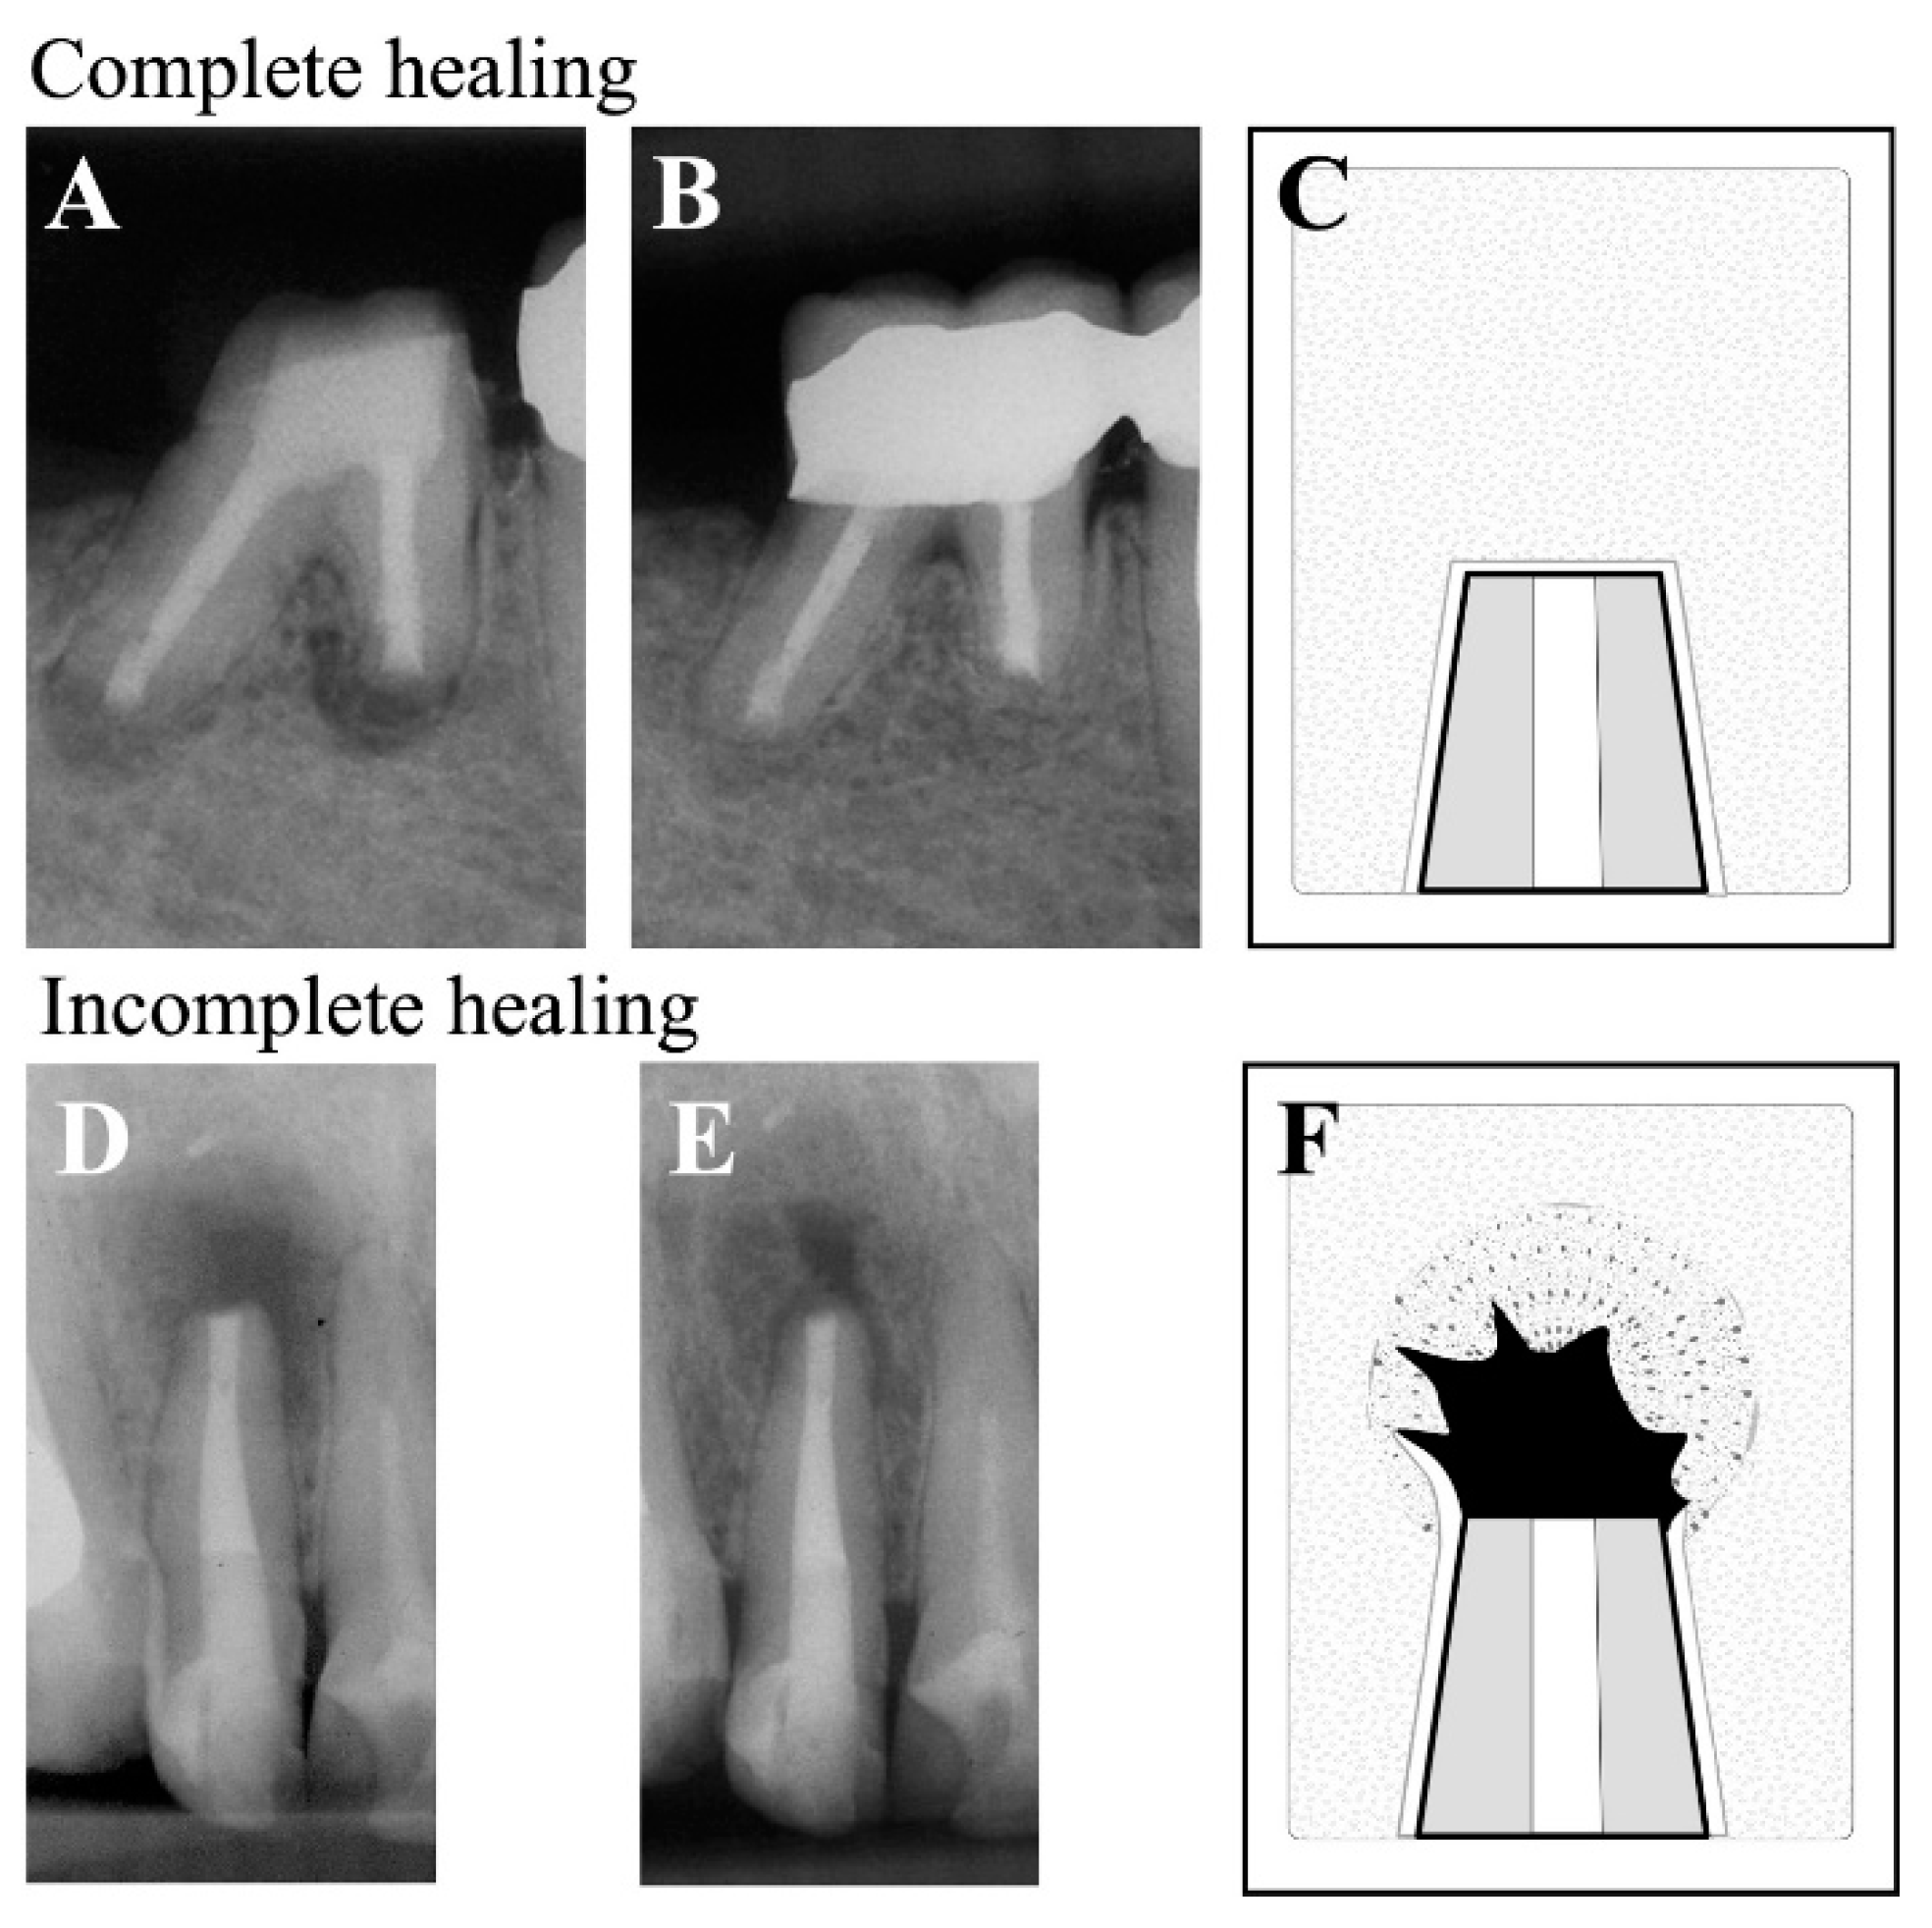

- Rud, J.; Andreasen, J.O.; Jensen, J.E. Radiographic criteria for the assessment of healing after endodontic surgery. Int J Oral Surg 1972, 1, 195–214. [Google Scholar] [CrossRef] [PubMed]

- Molven, O.; Halse, A.; Grung, B. Observer strategy and the radiographic classification of healing after endodontic surgery. Int J Oral Maxillofac Surg 1987, 16, 432–439. [Google Scholar] [CrossRef] [PubMed]